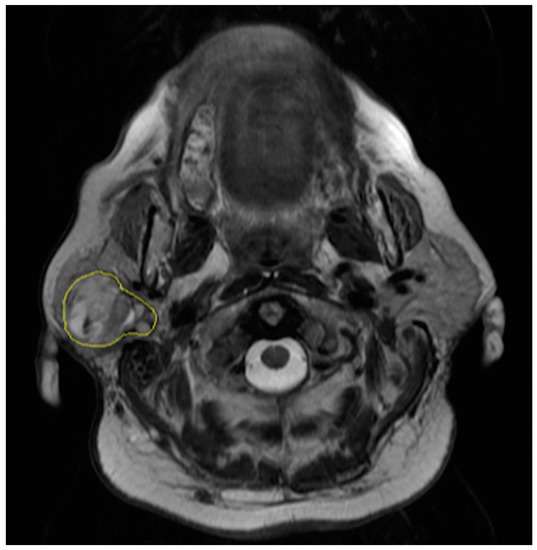

The regions of interest were manually drawn by a radiologist with eight years of experience in oncologic and head and neck imaging who was blinded to the results of the pathological examinations. The radiologist contoured the outer edge of the entire tumor slice by slice on axial fast spin-echo T2-weighted images (Figure 1). Contouring was performed so as to cover the maximum extent of the tumor without exceeding the lesion border.

Figure 1. Segmentation of axial T2-weighted magnetic resonance (MR) image of a 61-year-old woman with a pleomorphic adenoma of the right parotid gland.